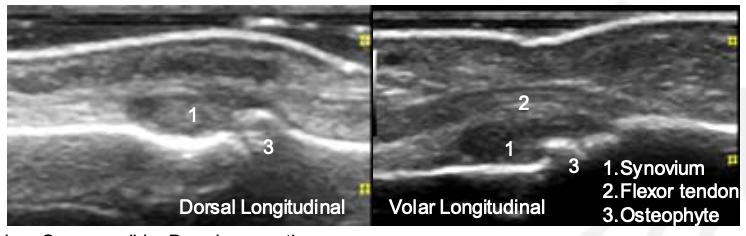

Grade The Synovial Hypertrophy

Grade this

B: grade 1 (up to 3 single signals — 1 confluent + 2 single — 2 confluent)

Minimal synovial hypertrophy up to the imaginary horizontal line connecting 2 joints; Power Doppler up to 3 single signals — 1 confluent + 2 single — 2 confluent

Grade 1: minimal

Moderate synovial hypertrophy protruding over the joint line along with concave surface; Larger than grade 1 but <50% of synovial hypertrophy covered by signals

Grade 2: moderate

Severe synovial hypertrophy producing beyond the joint line with convex surface; more than 50% of SH area covered by signals

Grade 3: Severe

Grade this doppler

Grade 2: Larger than grade 1 + <50% of SH area

Grade 3: >50% of the synovial hypertrophy is covered by signals

What grade is the synovial hypertrophy?

Grade 0

Grade this synovial hypertrophy

Grade 1: minimal within imaginary line between joint edges

Grade 2: moderate, extends over joint line with concave appearance

Grade 3: severe, extends beyond joint line with convex appearance